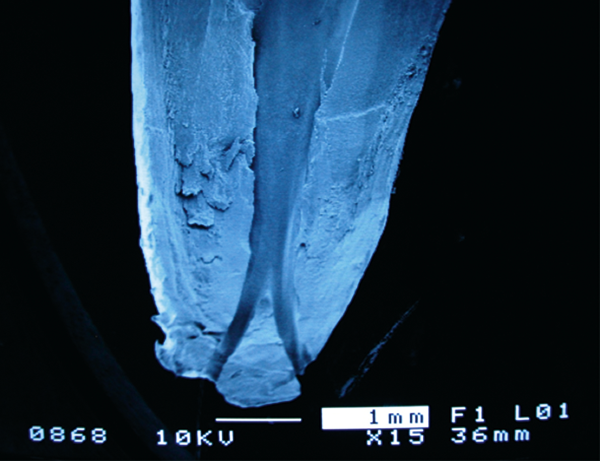

After the tooth was extracted, I was astonished. To my surprise, the root canal (the canal through which the nerve runs) was split in two.

Here, I would like to briefly explain about teeth. (Figure 1)